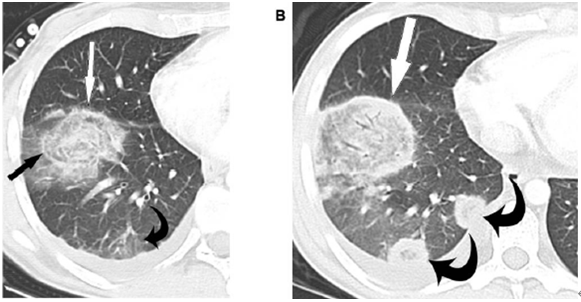

影像学特点

单发或多发的肺实变,常伴空洞。

底部贴近胸膜的楔形阴影。

单发或多发的小结节和晕征。

反晕征。

气管内病变。

其他:胸腔积液,累及纵隔、肋骨等。

图片

注:免疫缺陷的患者,左肺舌叶肺坏死,新月形空洞形成

注:底部贴近胸膜的楔形阴影

注:单发或多发的小结节和晕征

注:反晕征